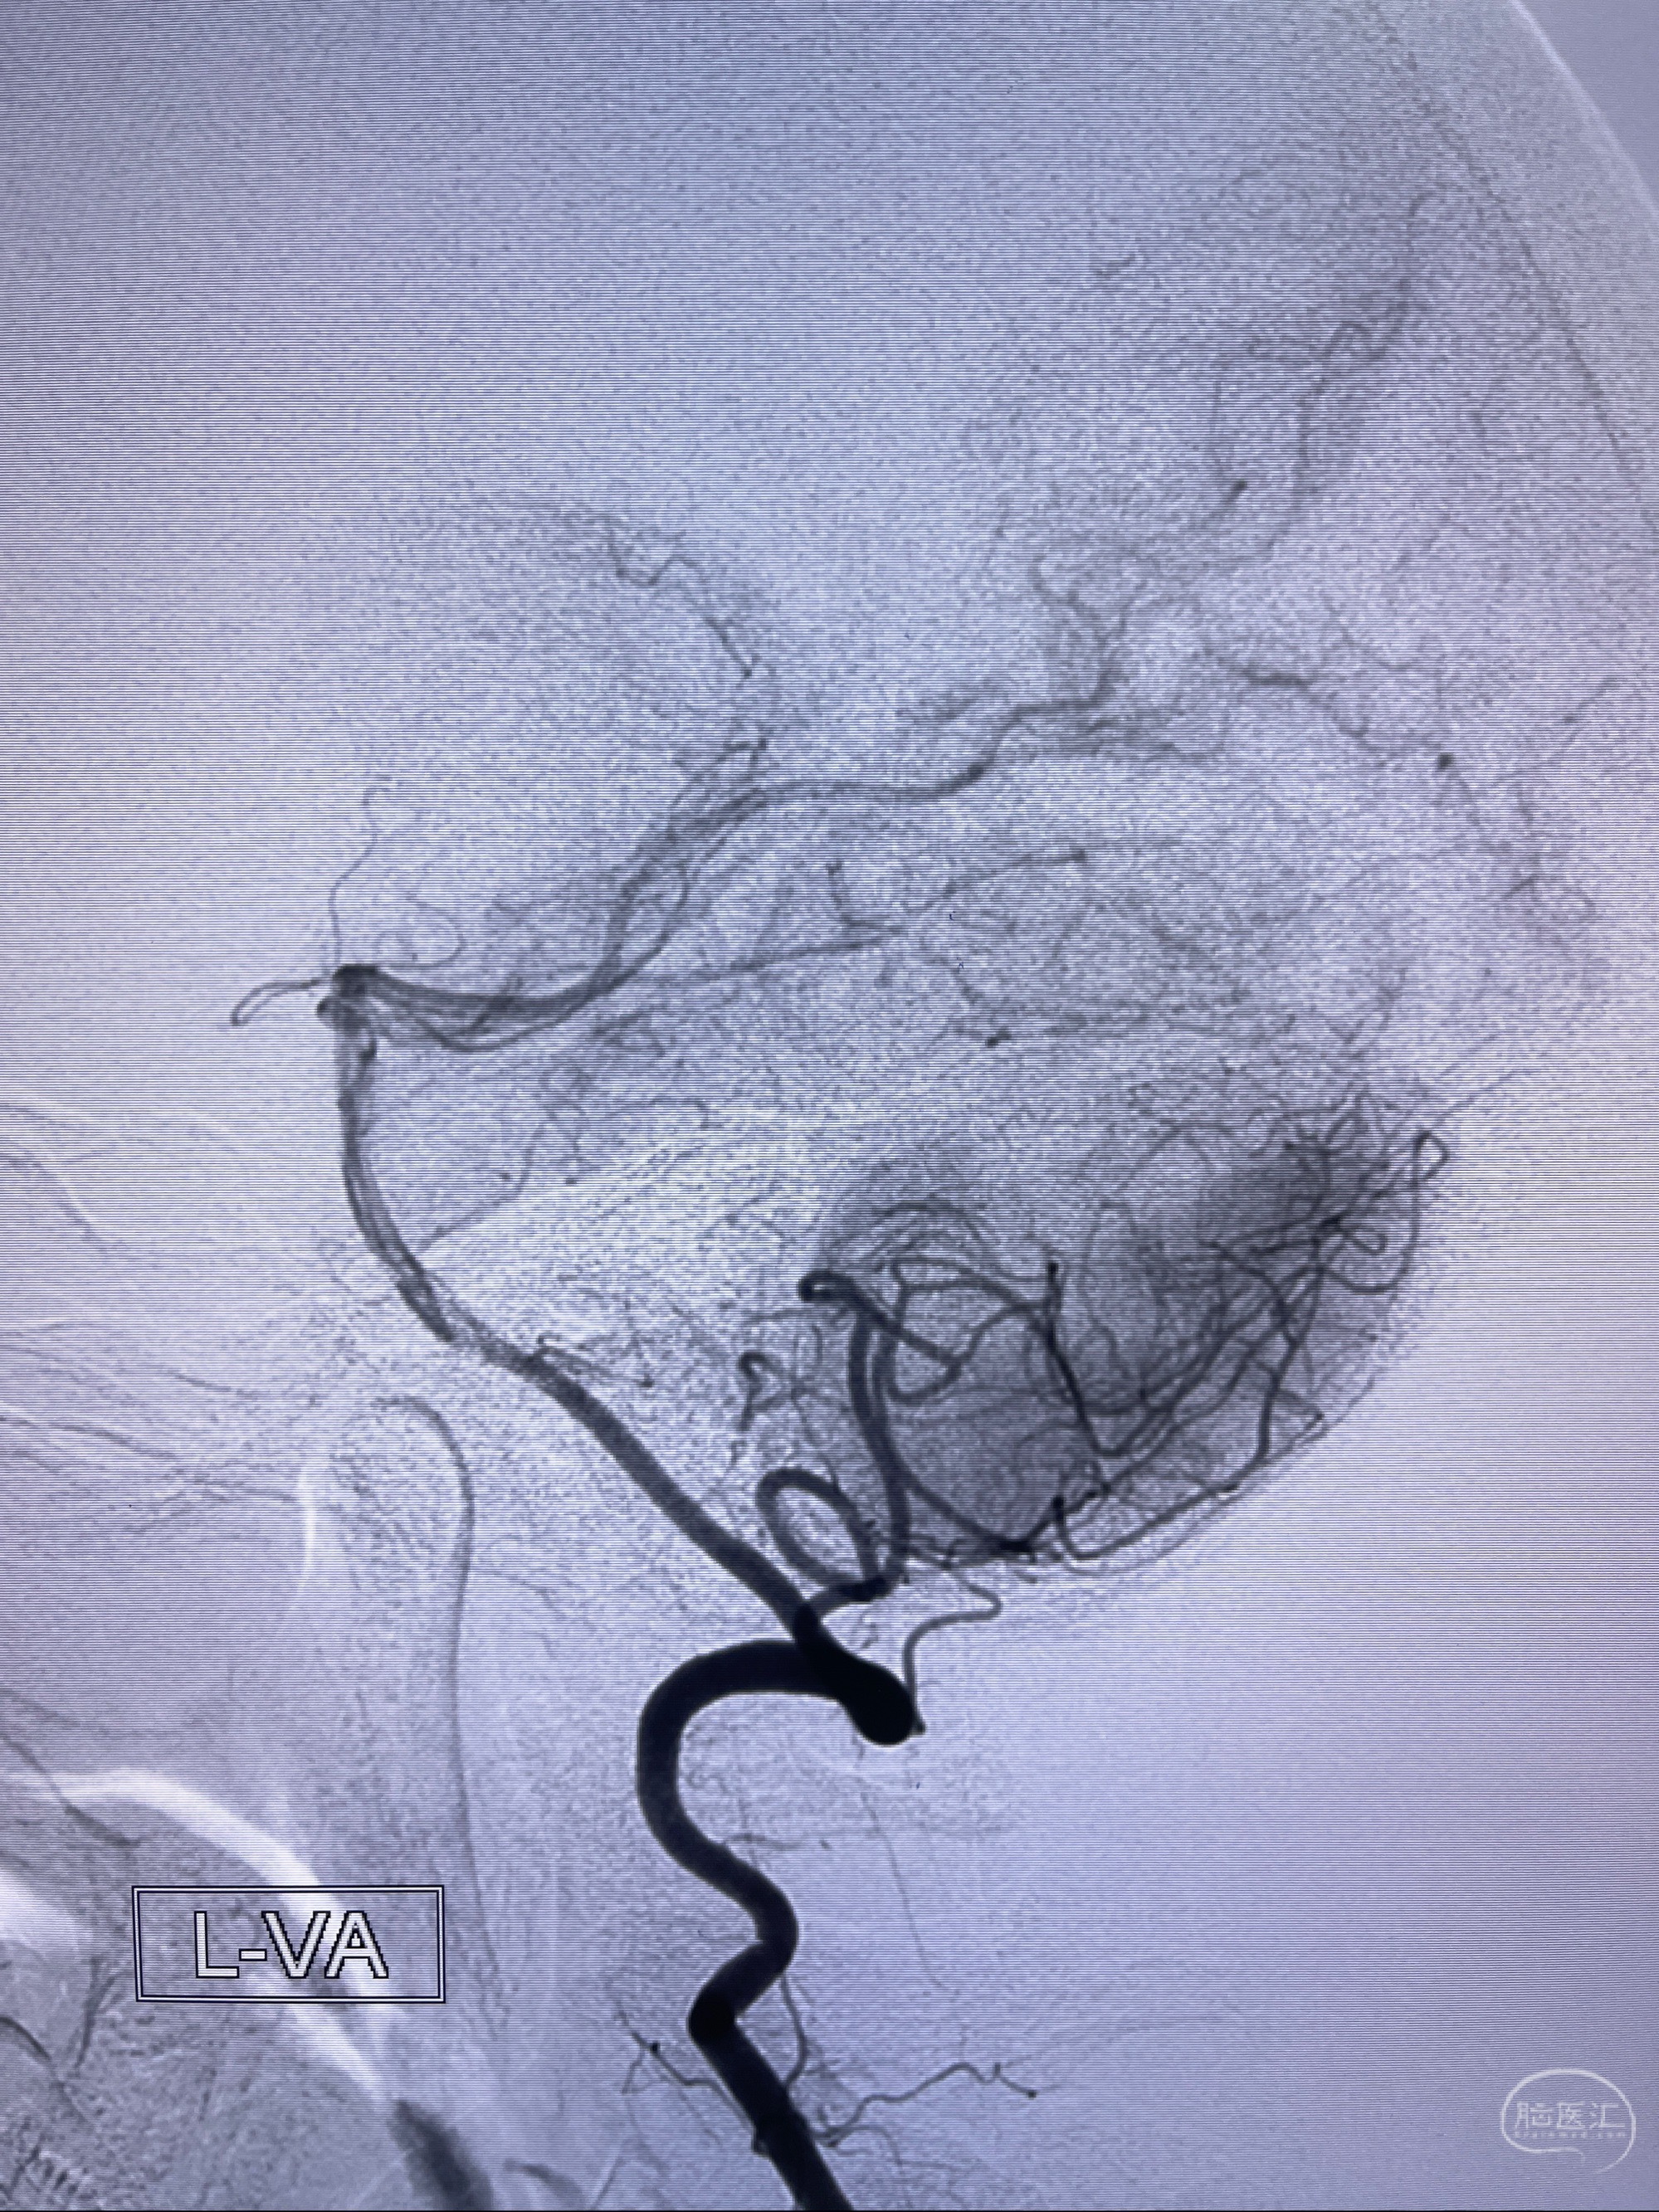

2023-08-14DSA:

左侧大脑中动脉动脉瘤,约2.6-2.8-3.4-2mm大小(瘤颈部、瘤体部、瘤高)

治疗策略:

1.左侧大脑中动脉动脉瘤,约2.6-2.8-3.4-2mm大小(瘤颈部、瘤体部、瘤高)

2.外科手术夹闭or介入支架辅助栓塞